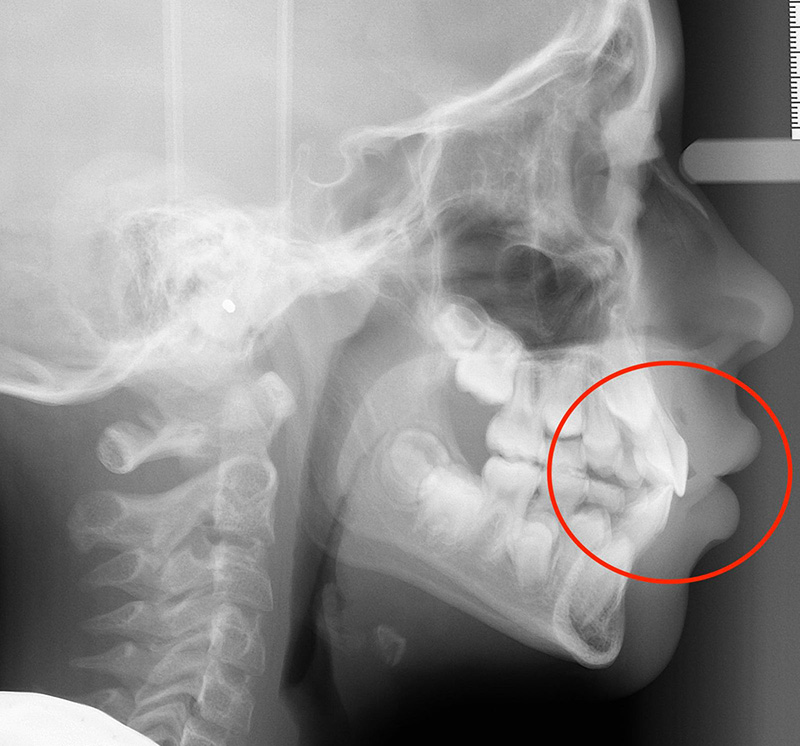

Actual Patient: Alexander

Alexander Before 4 Alexander After 4

Severe “Underbite”, Narrow Jaws, Adult Teeth Not Growing In

Alexander Before 1 Alexander After 1

Front View

Top View

Right & Left Sides

Front View Results

0 Month

6 Month

11 Month

Side View Results

Top View Results

Bottom View Results